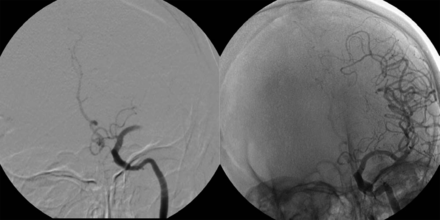

左侧颈内动脉注射了完整的大脑中动脉闭塞M1段(溶栓在脑缺血得分(TICI) 0),治疗动脉内的重组组织纤溶酶原激活物总共22毫克,完全再通(TICI 3)和几乎完全临床改善的NIH卒中量表评分2。